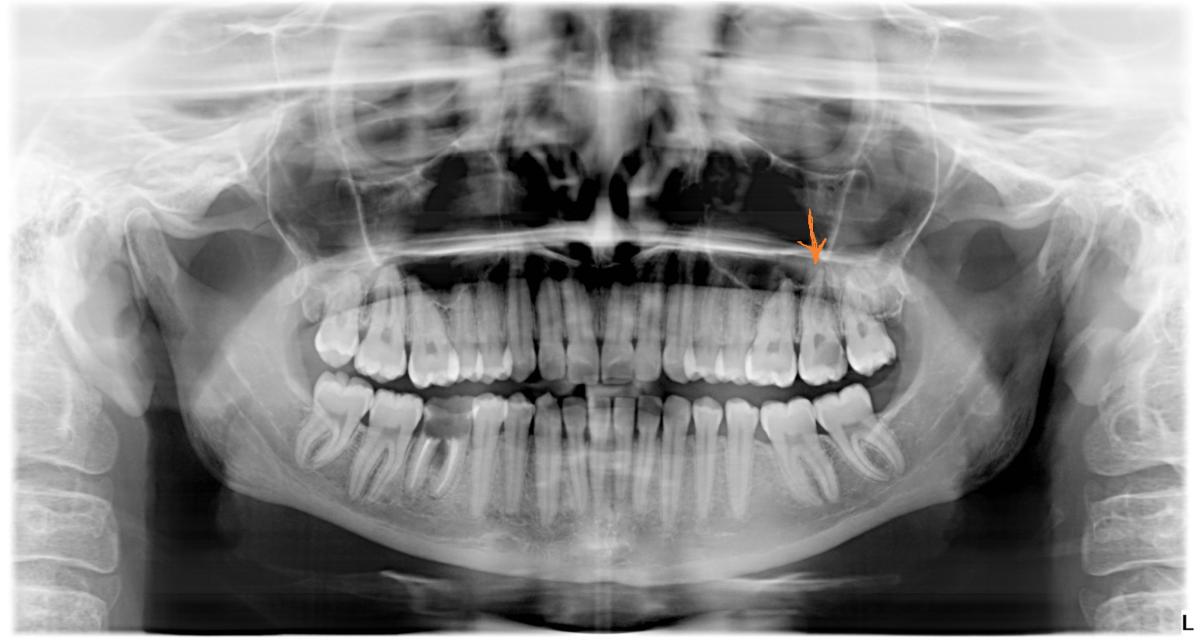

Дентальные снимки и диагностика кариеса